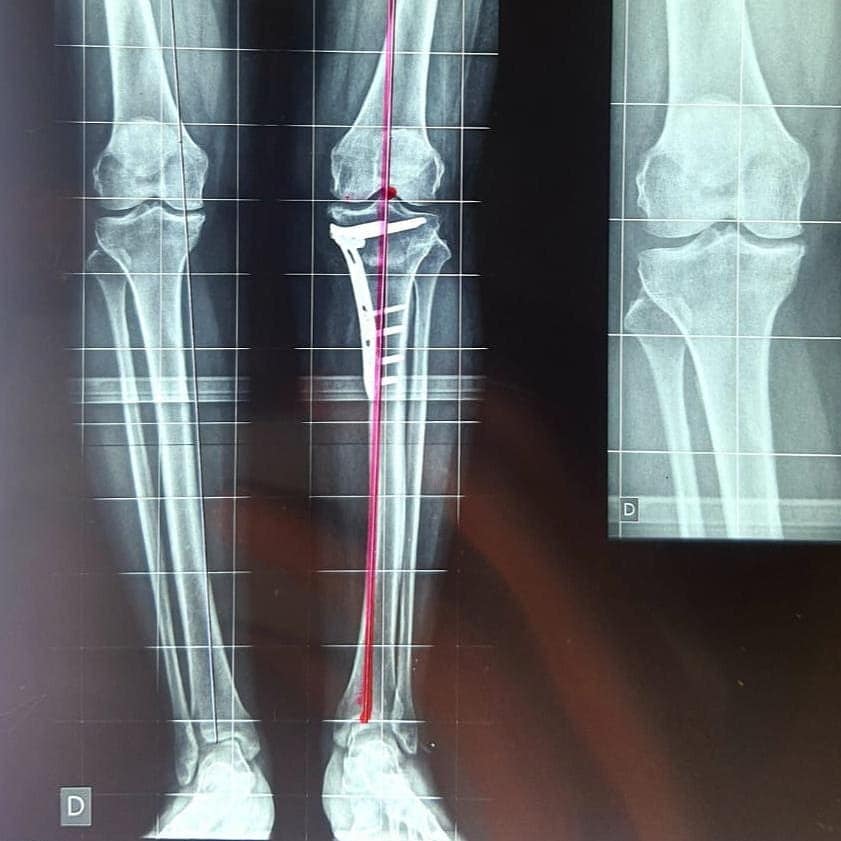

Bom, o joelho varo, conhecido também como geno varo ou “pernas de cowboy”, é uma condição normalmente genética em que os joelhos se mantém afastados mesmo quando a pessoa consegue encostar um tornozelo no outro, e acontece quando os ossos tíbia e fêmur não estão corretamente alinhados, dando a forma diferente à linha da perna..

Ao passar as imagens você verá o procedimento de Osteotomia, que é a correção da deformidade “joelho em varo”, realizado pelo nosso Especialista em Joelho o Doutor Danilo da Silva Lobo.